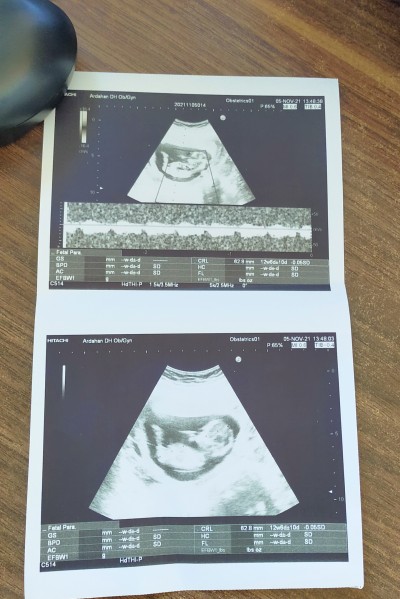

adet e göre 12+1 ultrasonda 12+6 çıktı sizde kız mi erkek mı ilk gebeliğim p

Bence kız bebis iki oğlumun da kafatası böyle değildi biraz daha farklı.oluyor ben kız hissettim kıza benzettim .sağlıkla al kucağına canım :)

Benimkine benziyor ultrason kagidin erkek canim benim bebeyim seninki de erkek olabilir